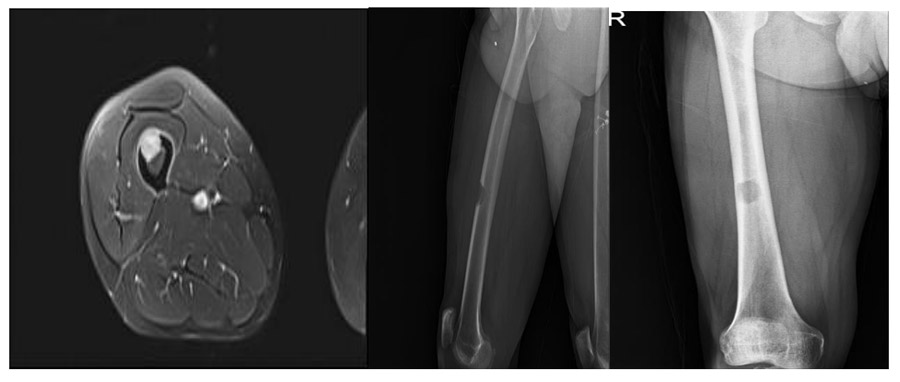

Before the surgery: X-ray and MRI show a focus of lytic metastasis in the middle (diaphysis) section of the right femur, causing destruction in the outer (cortex) portion of the bone.